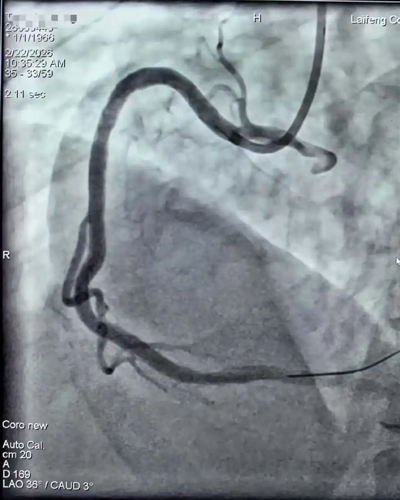

心血管内科:全天候诊,守护“心”的跳动

春节期间,情绪波动、劳累、饮食油腻等因素,使得心血管疾病如同隐匿的“杀手”随时可能发作。在心内科,这里的春节没有觥筹交错,只有仪器的滴答声。

医护人员严阵以待,急性心梗绿色通道24小时畅通。为了应对可能出现的急危重症,他们放弃了休假,时刻紧盯监护仪上跳动的曲线。每一次成功的抢救,每一次让濒临停摆的心脏恢复有力的搏动,都是他们对这个春节最深情的告白。

春节期间开通血管后植入支架